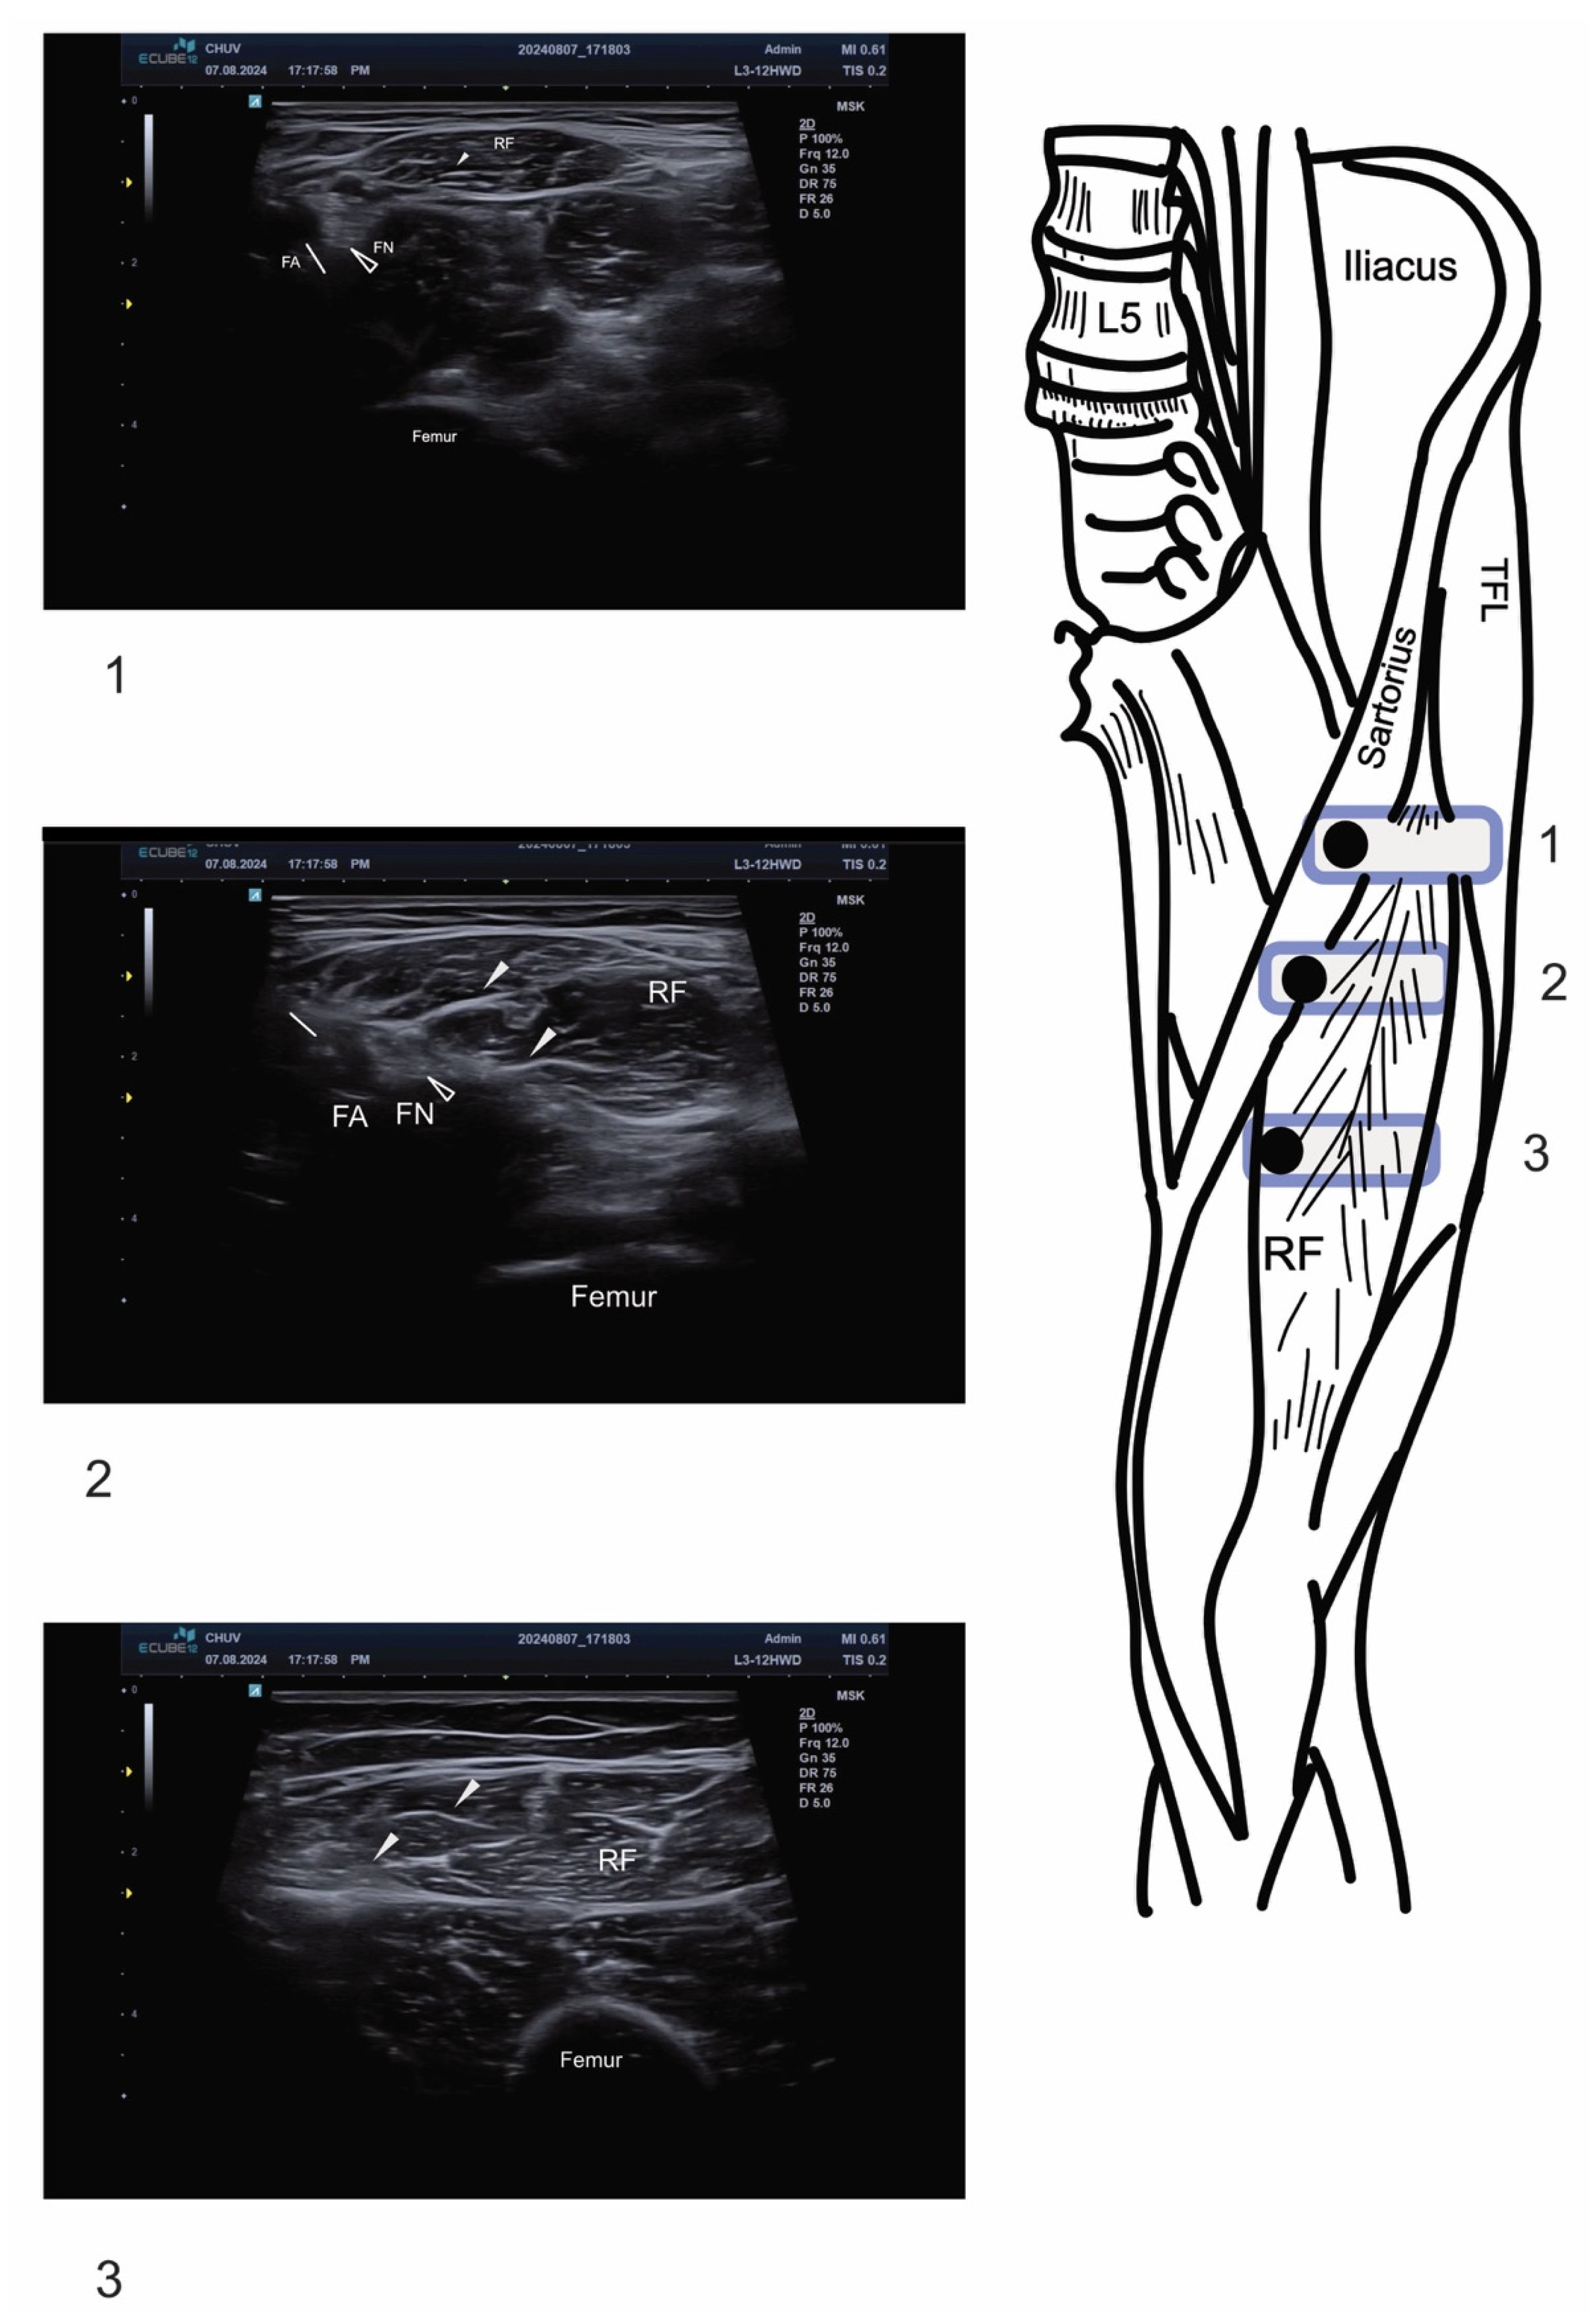

2.2. Ultrasound Technique and Anatomical Identification

2.3. Motor Nerve Branch Identification

2.4. Injection Technique